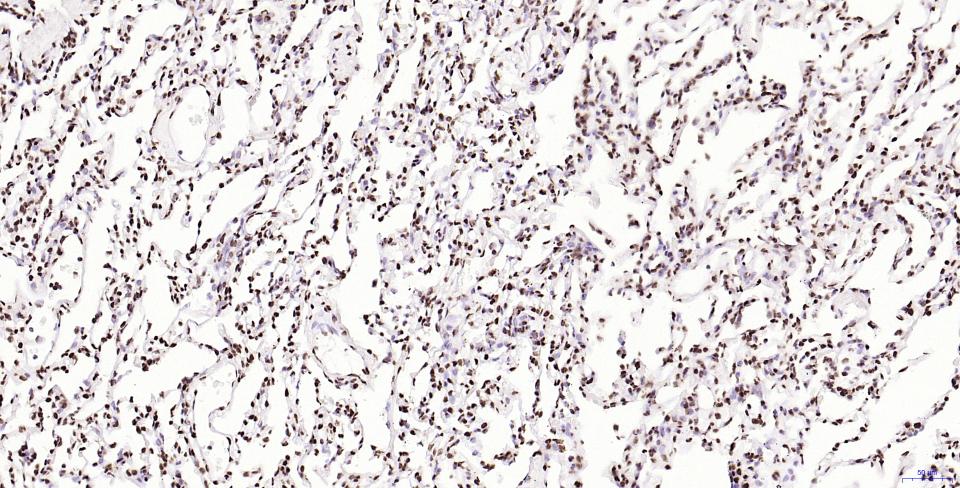

Paraformaldehyde-fixed, paraffin embedded Mouse Placenta; Antigen retrieval by boiling in sodium citrate buffer (pH6.0) for 15 min; Antibody incubation with Histone H2A.X Monoclonal Antibody, Unconjugated(bsm-61080R) at 1:200 overnight at 4°C, followed by conjugation to the SP Kit(Rabbit, SP-0023) and DAB (C-0010) staining.

Paraformaldehyde-fixed, paraffin embedded Rat Placenta; Antigen retrieval by boiling in sodium citrate buffer (pH6.0) for 15 min; Antibody incubation with Histone H2A.X Monoclonal Antibody, Unconjugated(bsm-61080R) at 1:200 overnight at 4°C, followed by conjugation to the SP Kit(Rabbit, SP-0023) and DAB (C-0010) staining.